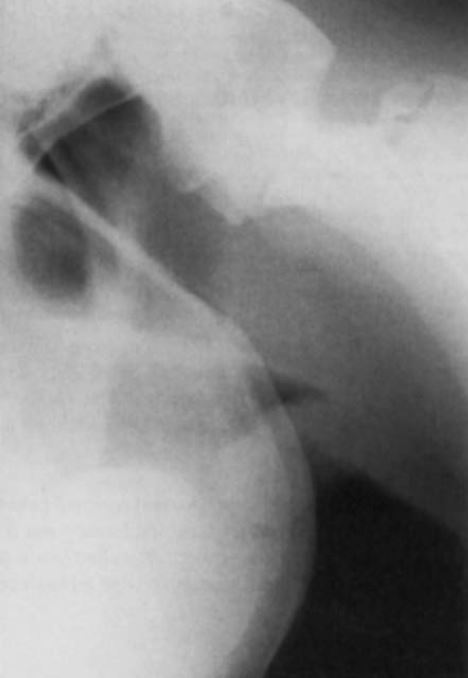

Horse is having gradual increase in dyspnea… what are your differentials?

Arytenoid chondritis - what it is.

Nasal cyst/polyp

retropharyngeal abscess

foreign body

neoplasia

epiglottic cyst.